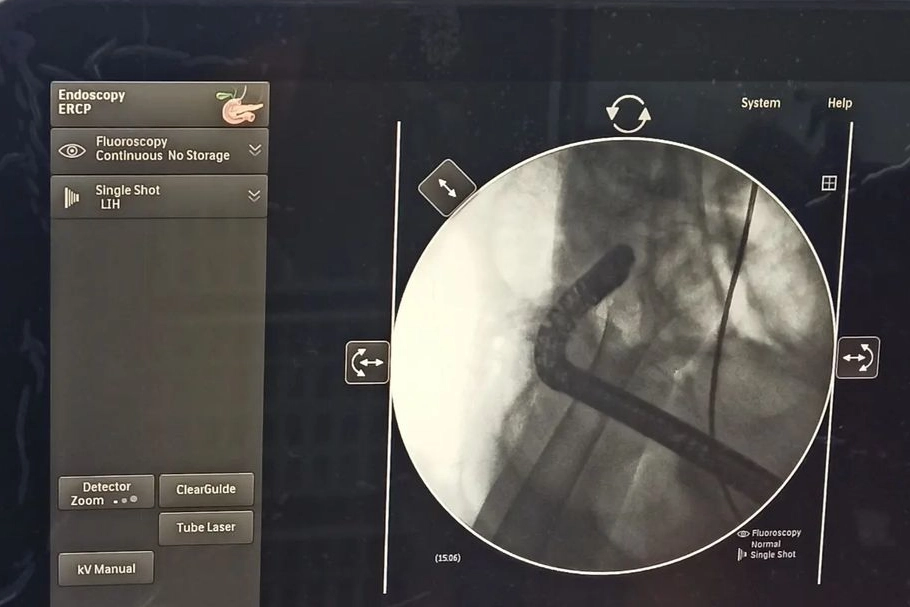

Hizmete giren ERCP cihazı hakkında bilgi veren Niğde Eğitim ve Araştırma Hastanesi Gastroenteroloji Uzmanı Dr. Çağatay AK; “ Bu cihaz hastanemiz için önemli ve gerekliydi. ERCP, duodeneskop denilen özel bir endoskopla gerçekleştirilir. Duodenoskop denilen ucunda ışıklı kamera sistemi bulunan cihaz ile ağız yolundan girilerek safra kanalı ve pankreas kanalının ortak açıldığı papilla denilen yere ulaşılır. Daha sonra milimetrik delikten ince uçlu katater denilen aletle girilerek safra kanalına ve gerekirse pankreas ulaşılarak kontrast madde verilir ve o bölgenin görüntülenmesi sağlanır. Kontrast madde safra kanalında bulunan taş, tümör ya da safra kaçakları ile tümör görüntüleme imkânı tanır. Böylece herhangi bir ameliyata gerek olmadan pankreas ve safra kanalında bulunan bu sorunlar tamamen ortadan kaldırılır. Bu işlemin burada yapılabilmesi bizim ve halkımız açımızdan çok büyük bir başarı.’’ dedi.

"Hastalar il dışına gönderilmeyecek. ERCP işlemi • Ana safra kanalından safra çamurunun, taşlarının temizlenmesi, • Safra yolu veya safra yolu ağzı darlıklarının açılması, • Safra yolunu daraltıp tıkayan kanserlerde stent konarak normal safra akışının sağlanması, sarılığın giderilmesi, • Sklerozan kolanjit gibi bazı hastalıkların tanısında, • Bazı pankreas hastalıklarının tedavisinde (pankreatik stent uygulaması, kanalı taşlarının temizlenmesi vs), • Safra yolu parazitinden şüphelenilen durumlarda, • Tıkayıcı sarılıkların, tedavisinde kullanılmaktadır. Bu ünitenin hastaneye kazandırılmasında emeği geçen herkese teşekkür ederim.” diye konuştu.